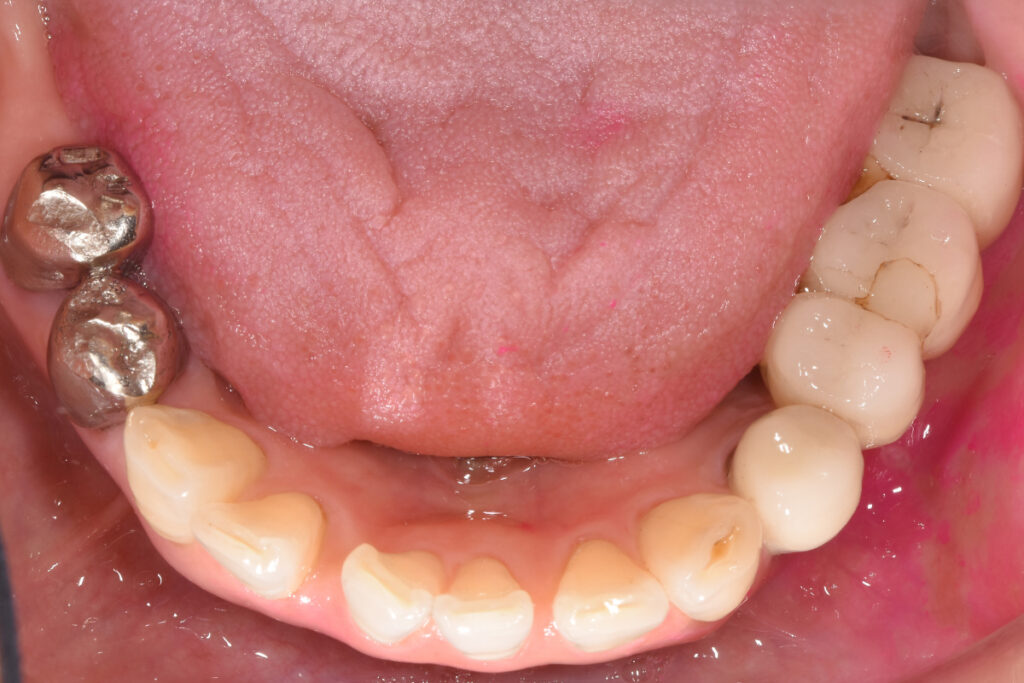

症例1|骨量不足で断られたケース

――「骨が足りない」というNOを、どう再定義したか

■背景

50代女性。下顎奥歯の欠損。片側咀嚼が続き、噛み合わせ全体への不安が強まっていました。他院でインプラント相談を行いましたが、「骨量が足りないため難しい」と説明され、治療を断念しました。

■問題点の整理

- 骨量が少ないこと自体は事実

- ただし、本来検討すべきは

- 骨造成を行えば成立する可能性があるのか

- 成立させた場合に長期安定が見込める条件か

- つまり「骨が少ない」という確認だけで終わり、成立条件の判定がなされていなかった

■当院での判断

吉留英俊が行ったのは、「できるかどうか」ではなく、「成立させた場合に安定するかどうか」の検討です。

- 骨造成(GBR)を併用した場合の骨の獲得量の見込み

- 咬合負荷の方向(どの方向に力がかかるか)と分散の設計

- 術後管理を継続できる条件(通院、清掃、生活習慣)

これらを精査した結果、条件付きでできると判断しました。

■選択した治療

- 骨造成(GBR)を併用したインプラント治療

■結果としての状態

治療は完遂しました。現在は定期管理下で、機能的・構造的に安定した状態を維持しています。患者の実感は「噛める」だけではありません。「これ以上悪化させないで済む」という安心が残りました。